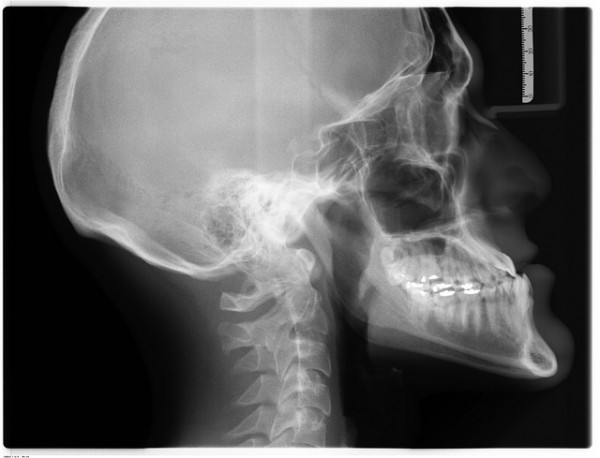

Diagnostic & interventional radiology